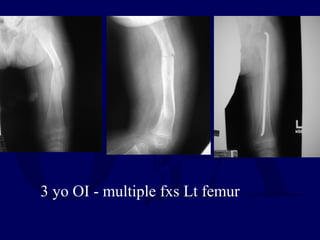

3 yo OI - multiple fxs Lt femur

OI